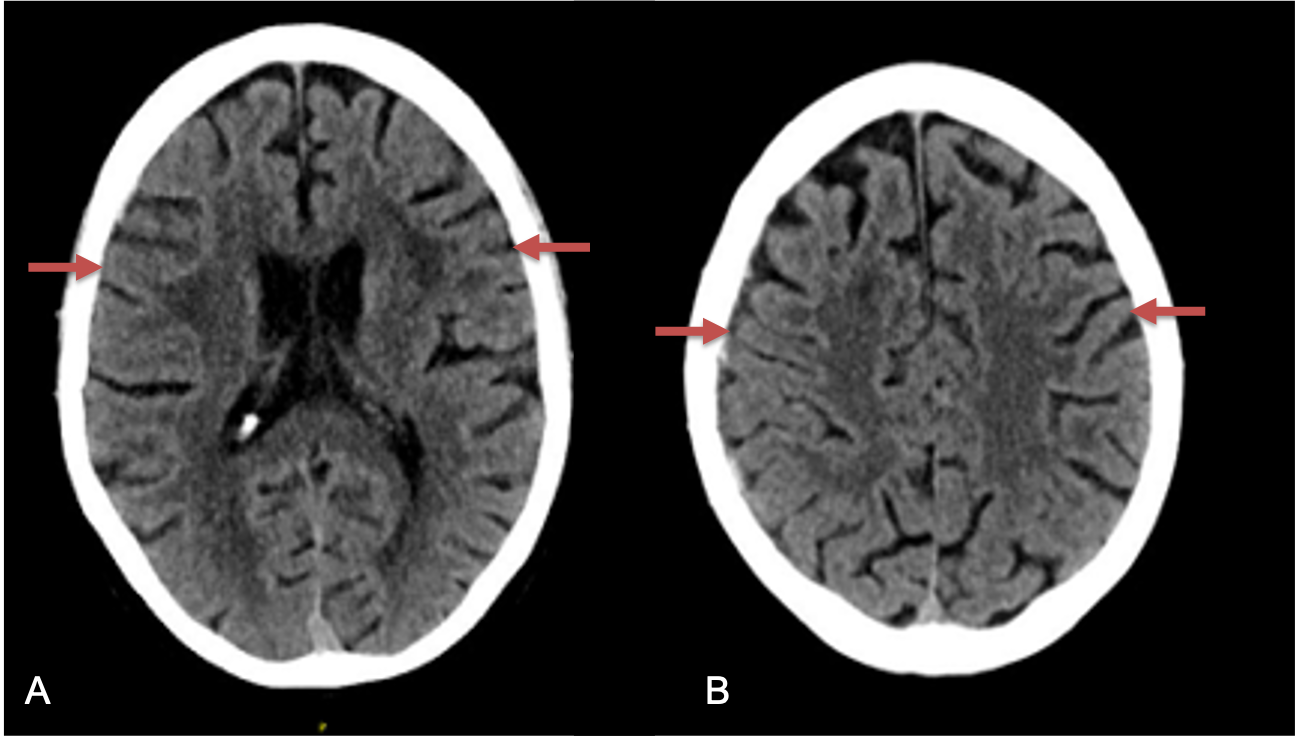

CT follow-up at 1 week demonstrates early resorption. 2 weeks post MMA embolization, resolution of the left subdural collection with new small thin acute hemorrhage in an otherwise stable right subdural collection is observed (Figure 3. A and B).

Figure 3. A) 1 week post MMA embolization demonstrating decreasing thickness bilaterally B) 2 weeks post MMA demonstrates resolution on left, with small new acute component on right with overall decreased thickness.